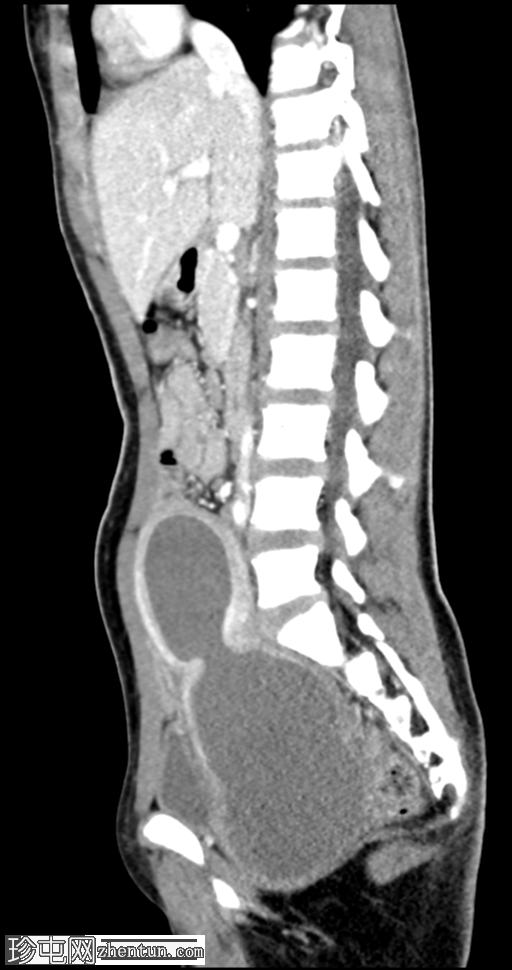

矢状C+门静脉期

可见明显扩张的充满液体的结构从阴道管延伸,与宫颈相通,进入中度扩张的子宫内膜腔,其上缘位于L4椎体。

内容物为均匀的高衰减液体(约35-55 HU),与血液密度一致。

该液体使膀胱向前移位,并移位邻近的肠管。

无腹部游离液体、肠梗阻、淋巴结肿大或肾积水的证据。